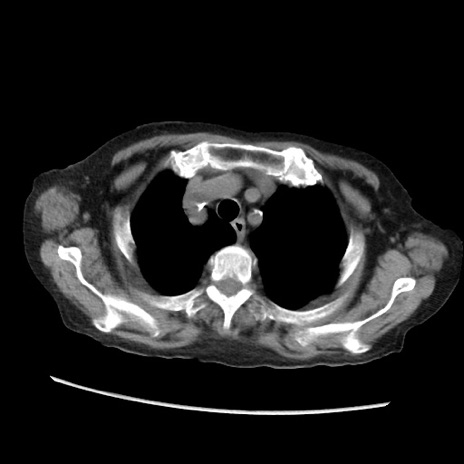

症例31(横断像)

【症例】80歳代 女性

【主訴】腹部膨満感

【現病歴】他院にて肝硬変にてフォロー中。1週間前から便秘、腹部膨満感、臍部腫瘤あり受診となる。

【既往歴】肝硬変

【身体所見】腹部膨隆あり、皮膚変化なし、疼痛なし。

【データ】WBC 4600、CRP 0.25